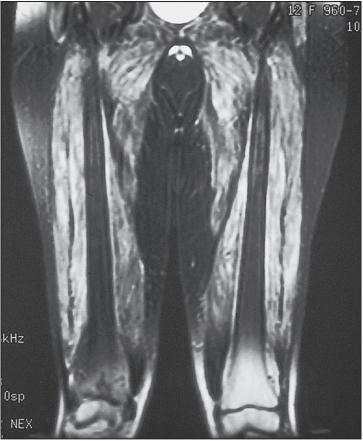

肌肉活检的光镜检查

但是如何做肌肉活检?仅仅根据症状就行肌肉活检是不妥的。尤其采用医生体检按压肌肉寻找肌肉活检部位。这是因为临床按压本身可能误导肌肉活检结果。为此,予以磁共振(MRI)检查肌肉是必要的。因为MRI对早期肌组织病变和钙质沉着敏感。采用T2加权和压脂序列可以清楚显示病变范围,提高肌电图及肌活检的阳性率。虽然「皮肌炎和多发性肌炎」临床表现为对称性近端肌肉受累,但MRI可以呈现不均匀和不对称性。MRI阳性改变在一些血清肌酶正常的「皮肌炎和多发性肌炎」中亦不少见。因此, 可用于评估疾病活动性、 累及损害和对治疗的反应。

一儿童皮肌炎的MRI压脂图像显示,注意白色提示肌肉炎症